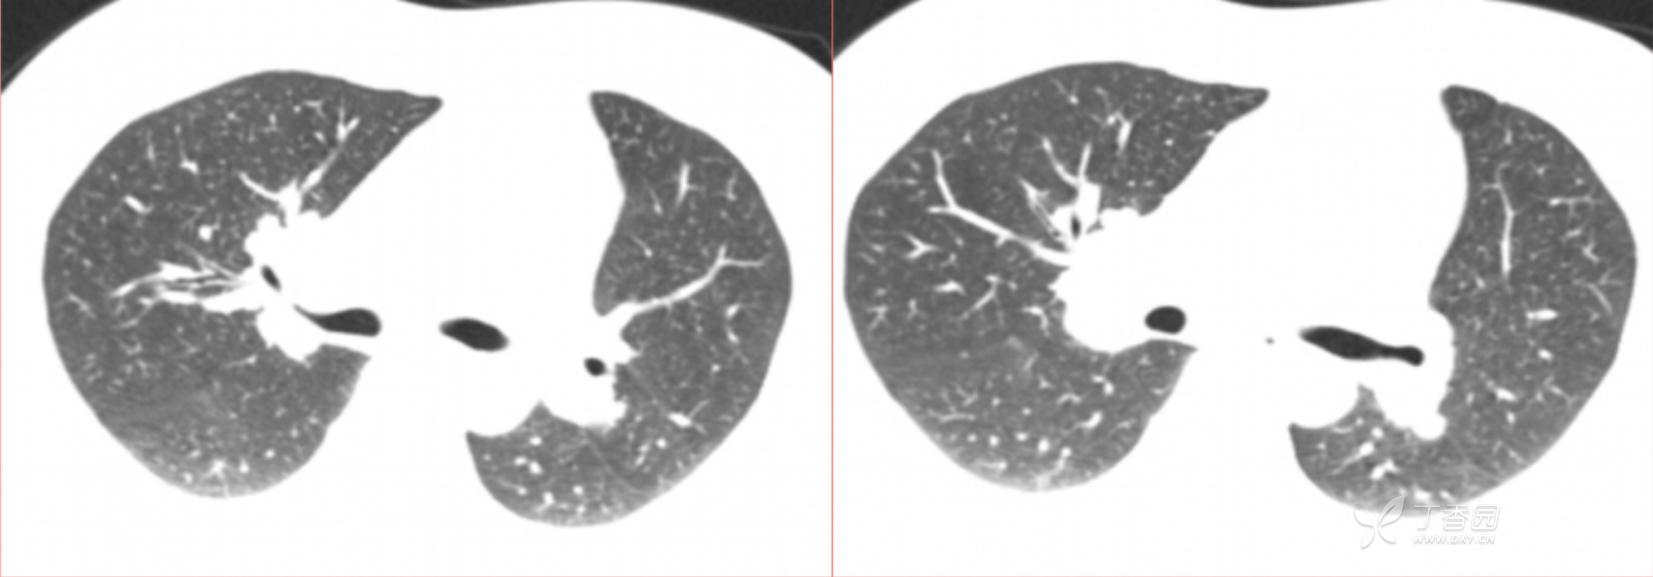

1月特别精彩病例|阵发性刺激性咳嗽,咳少量白色粘液痰1周,期待你的挑战【结果公布】

患者年龄:34岁

简要病史:患者一周前无明显诱因出现阵发性刺激性咳嗽,咳少量白色粘液痰,咳嗽无明显昼夜节律性,无发热、畏冷、寒战,无头痛、胸闷、胸痛,自行服药后 (具体不详) 症状无缓解,3天前当地医院胸片检查示右上病变

辅助检查:肺肿瘤标志物: 神经元特异性烯醇化酶(NSE): 35.72ng/ml(参考值0-16.3);非小细胞肺癌相关抗原211、癌胚抗原、糖类抗原125、铁蛋白、鳞状细胞癌抗原未见异常